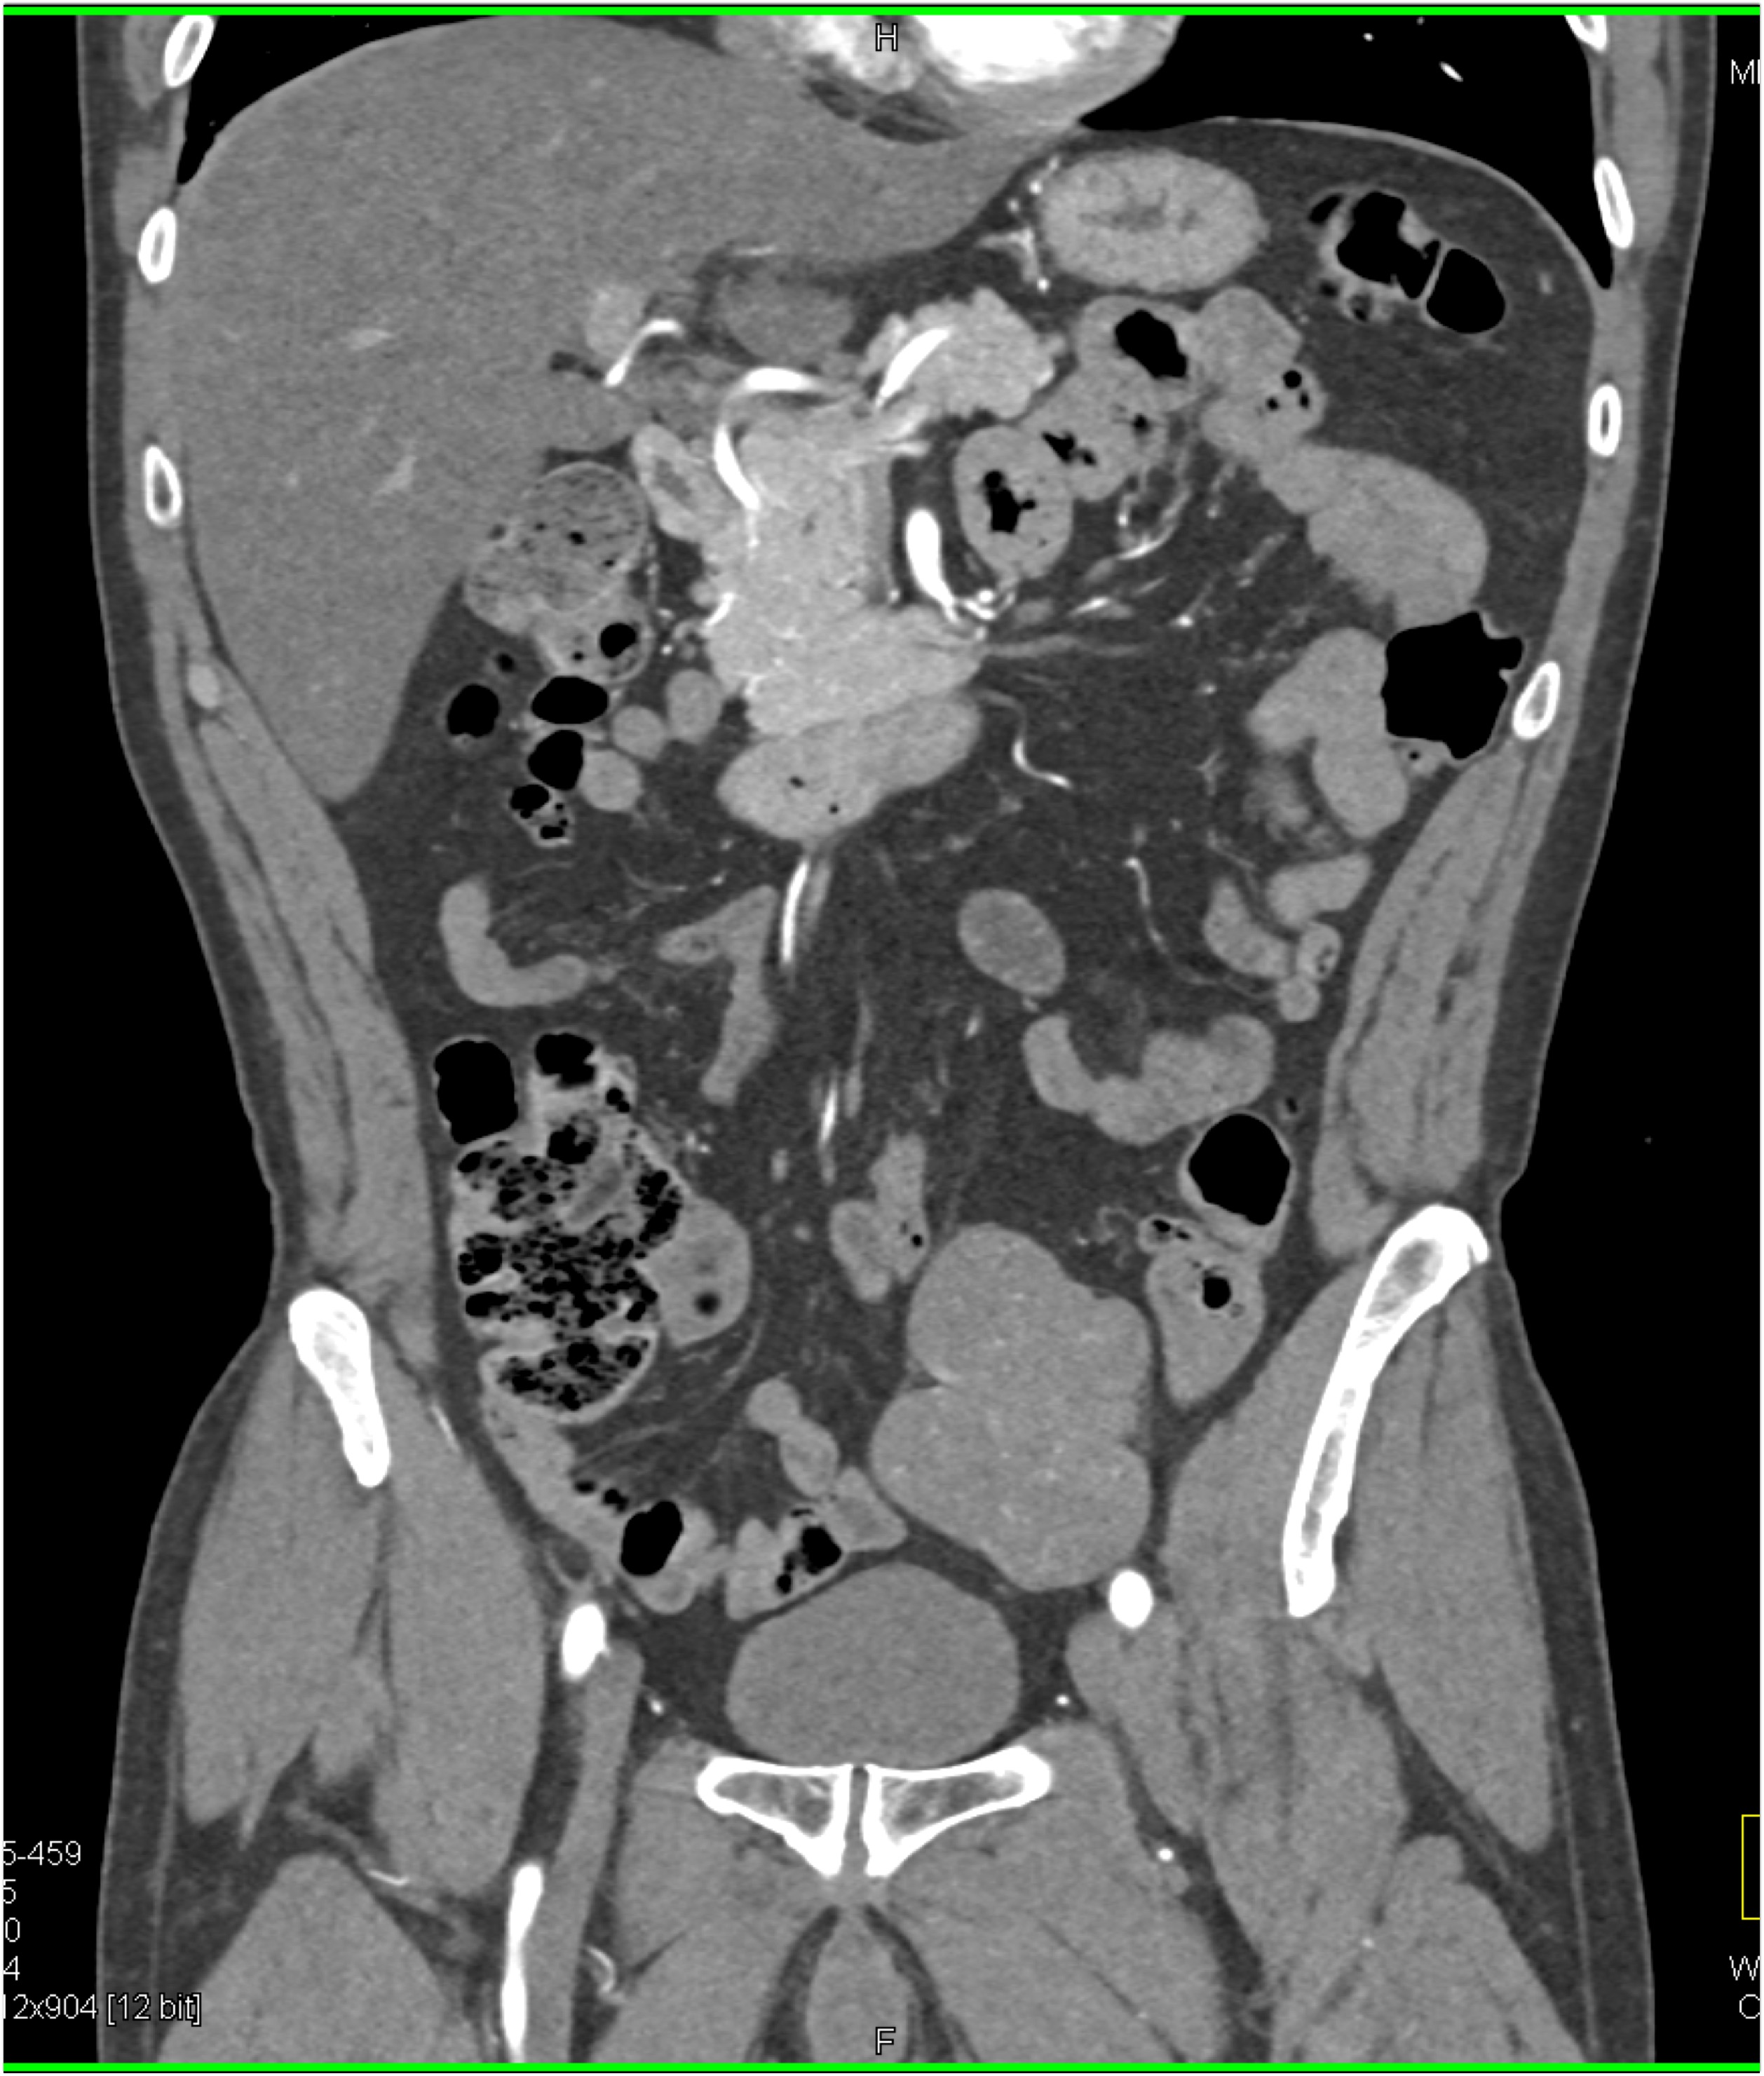

7) The least likely diagnosis in this case is?

lymphoma

adenocarcinoma cecum

carcinoma terminal ileum

undistended normal colon